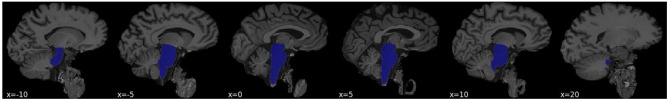

Methods: In a series of multiple linear regressions, we assess the volume of the brainstem in two asymptomatic at-AD-risk samples, assessed via the presence of either mild cognitive impairment (MCI, N = 148), or extremely high polygenic risk (N = 13) with matched demographics (mean age = 67 [range 58-76], in both cases). We further determine the strength of the association, compared to 150 other structural MRI features.

Results: We observed brainstem volume reductions (MCI: b = -0.29, P = 0.018; Genetic risk: b = -1.29, P = 0.002) in both samples. The magnitude of each preclinical AD marker (MCI / AD-polygenic risk)- brainstem association was empirically larger (Z > 2.3, P < 0.05, in both cases) than 150 frequently segmented MRI features. We further replicate the negative AD-polygenic risk score- brainstem association in UK Biobank (N = 31968; b = -0.002, P = 0.03), with weaker evidence that the association was larger than all other MRI features (Z = 1.622; P = 0.052).

Conclusions: These observations suggest that AD risk, assessed via the presence of MCI or extremely high AD-polygenic risk score is linked to reduced brainstem volume before most typically observed morphological brain alterations. This conforms with evidence implicating the brainstem as one of the earliest sites of morphological neurodegeneration and provides a plausible biological mechanism linking prodromal autonomic symptoms to AD risk in later life. These observations warrant future investigation into the molecular correlates of AD-linked brainstem dysfunction, assessment as a candidate biomarker, and the exploration of brainstem mediated treatment strategies in AD prevention.